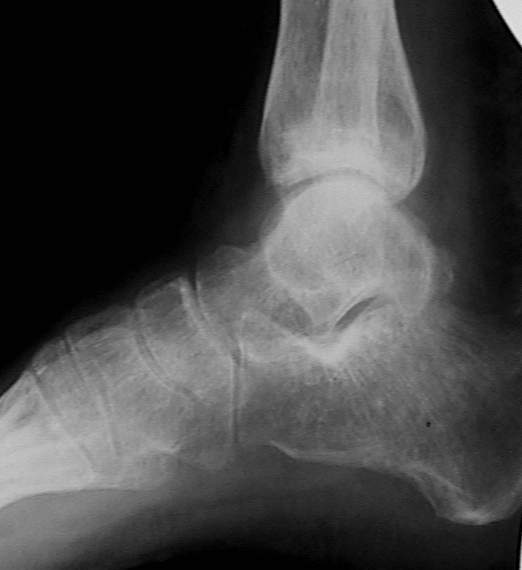

У больного травма в августе 2001 г. Лечился консервативно, Проводилась иммобилизация гипсовой лонгетой 3 мес. В последующем местное лечение. Остается контрактура боли в области наружной лодыжки. Направлен в наше отделение в конце января 2002 г Планируется костная аутопластика, остеосинтез пластиной, винтами перелома наружной лодыжки. Решается вопрос о коррекции неправильно сросшегося перелома внутренней лодыжки. Рентгенограммы: фас; профиль; план Сергей Зырянов

Насчет наружной лодыжки - не уверен, что вообще надо что-то делать.

на снимке, кстати, срезан ее дистальный отдел, и правильность взаимоотношений с таранной костью не оценить. Если они правильные - я бы присоединился к мнению об оставлении ее покое.

А вот укорочение внутренней, похоже, привело к натяжению дельтовидной связки и гиперпрессии в медиальном отделе сустава, и уже сейчас там

видно сужение щели. Так что есть смысл обратить внимание на ортопедическую профилактику деформирующего артроза.